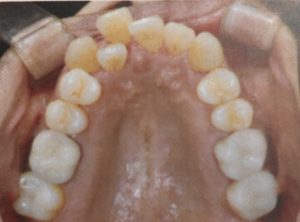

【上あご】

<矯正前 2018/06/30>

【下あご】

<矯正前 2018/06/30>